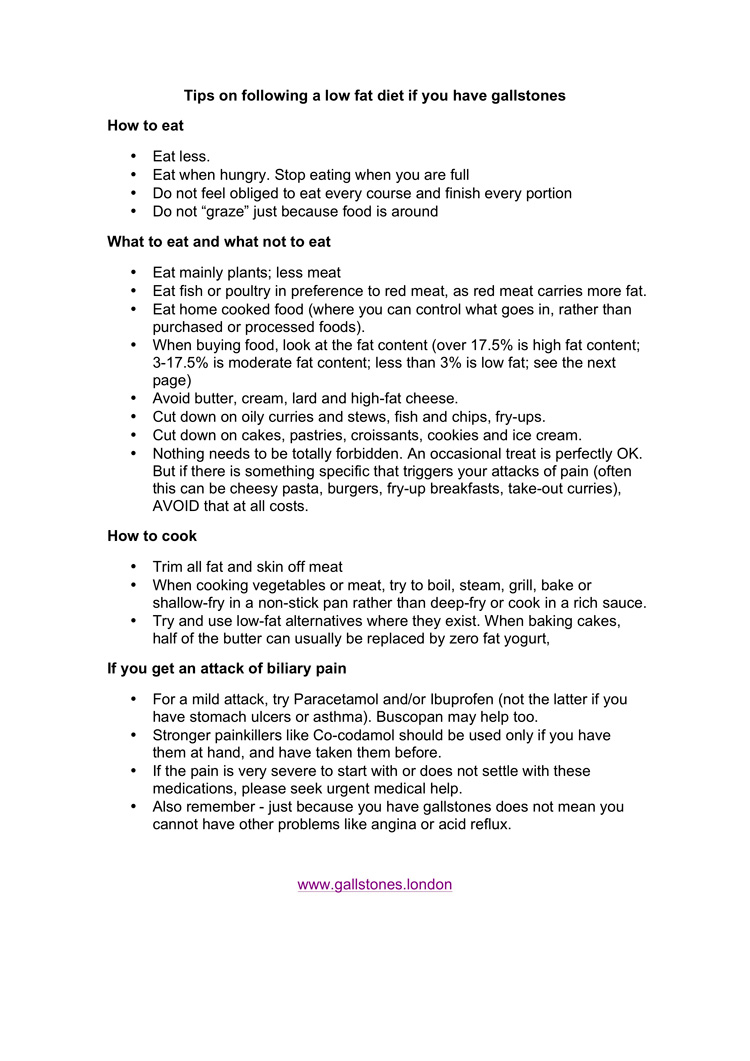

Is there a particular diet I should follow if I have gallstones?If certain fatty foods have triggered your attacks of pain, you should obviously avoid those. In general, you will be better off if you adopt a low fat diet. This will not get rid of your gallstones, but may reduce the severity and frequency of your attacks of pain. Here are some tips:

How to eat- Eat less

- Eat only when hungry; stop eating when you are full

- Do not feel obliged to eat every course and finish every portion

- Do not “graze” just because food is there around you

What to eat and what not to eat- Eat mainly plants; less meat

- Eat fish or poultry in preference to red meat, as red meat contains more fat.

- Eat home cooked food (where you can control what goes in, rather than purchased or processed foods).

- When buying food, look at the fat content (over 17.5% is high fat content; 3-17.5% is moderate fat content; less than 3% is low fat; see the next page)

- Avoid butter, cream, lard and high-fat cheese.

- Cut down on oily curries, fish and chips, fry-ups, burgers.

- Cut down on cakes, pastries, croissants, cookies and ice cream. Nothing needs to be treated as totally forbidden. A small portion of something as an occasional treat is perfectly OK.

- But if there is something specific that triggers your attacks of pain (often this can be cheesy pasta, burgers, fry-up breakfasts, take-out curries), AVOID that at all costs.

How to cook- Trim all fat and skin off meat

- When cooking vegetables or meat, try to boil, steam, grill, bake or shallow-fry in a non-stick pan rather than deep-fry or cook in a rich sauce.

- Try and use low-fat alternatives where they exist. When baking cakes, half of the butter can usually be replaced by zero fat yogurt,

If you get an attack of biliary pain

For a mild attack, try Paracetamol or Ibuprofen (assuming you have no allergies to either of these drugs and no asthma) as well as some anti-acid medication (for example Gaviscon or Omeprazole). Buscopan may help too. Stronger painkillers like Co-codamol or Diclofenac should be used only if you have them at hand, and have taken them before. If the pain is very severe to start with or does not settle with these medications, please seek urgent medical help. Please remember - just because you have gallstones does not mean you cannot have other problems like angina or acid reflux.

Below is a list of the fat content of common food items: